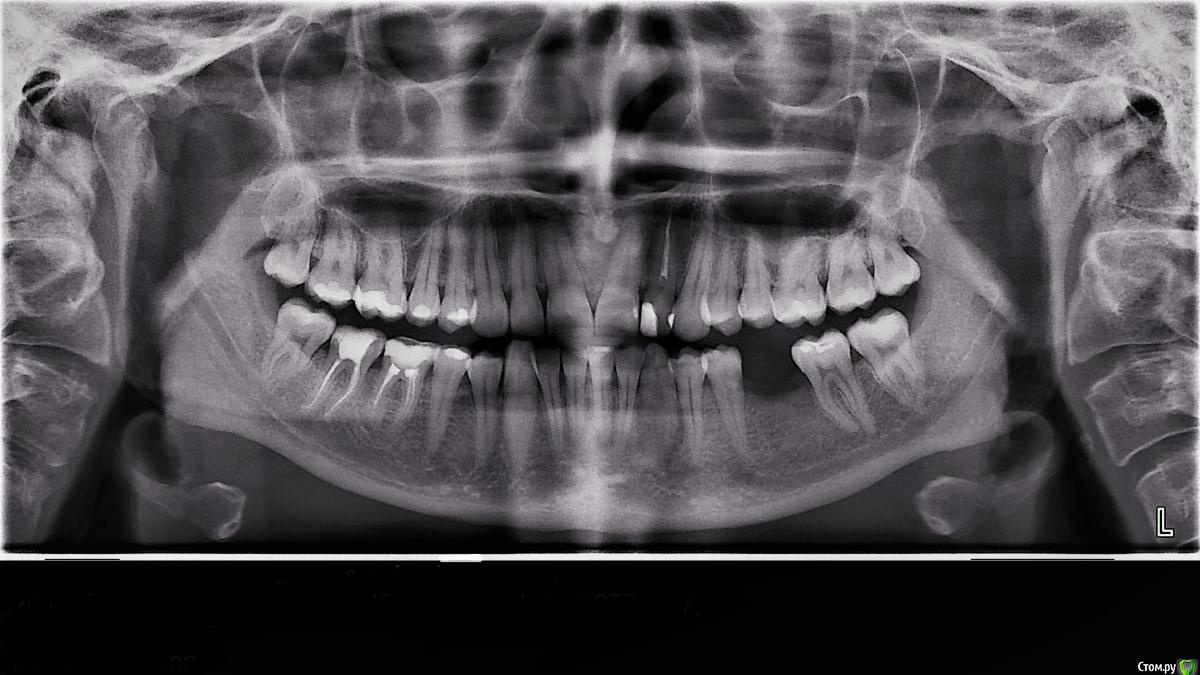

Есть подозрение, что с первым зубом на нижней челюсти что-то не так. Когда-то край зуба у меня чуть стерся и зуб стал очень реагировать на все. Пошла запломбировать, после он уже не болел, но пломба словно стянула все или не знаю что это, но, если я на зуб давлю, то он как бы чешеться. Я к этому привыкла, прошло так пару лет уже. А тут сделала рентген и как будто там что-то темное ростет. Зуб не болит. Сделали тест на холод -50°, зуб молчал. Врач говорит, что помер зуб мой, оказывается. Возможно такое без боли? Вы тоже видите там "труп"?

Доктор все правильно говорит. По снимку вокруг корня есть воспаление, это говорит о том что нерв не живой, отсутствие температурной реакции это подтверждает.